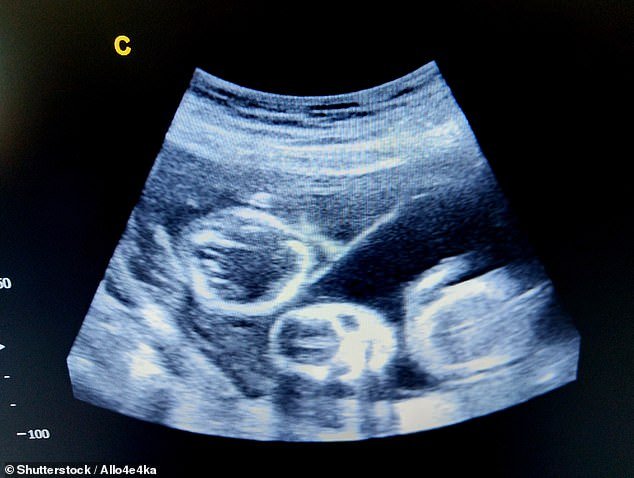

Sin embargo, durante el escaneo de 11 semanas se notó que los niños no parecían idénticos, lo que probablemente significaría que no provenían de un embrión dividido.

Luego, el escaneo de 16 semanas se confirmó que los niños no tenían el mismo sexo.

Explicó: “Si el embrión está dividido, los gemelos tienen que ser lo mismo, por lo que el género diferente indica que no lo son”, explicó.

“Sus embriones fueron probados genéticamente antes de la transferencia de la pareja para que la clínica conociera el género de su bebé”.

La Sra. Williams dice que ambos niños serán evaluados en ADN después de su nacimiento

“Por supuesto, los probaremos independientemente del nacimiento porque cuando vayas a la corte y me quites a su bebé y a mi esposo, entonces necesitas ADN para mostrarles” “